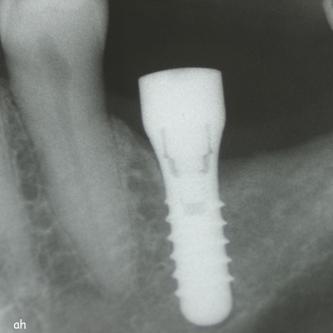

Exemple 14: 6 mois plus tard, l'implant est introduit dans cette greffe sans toucher le sinus.